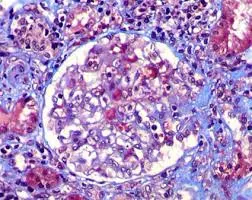

Intoxicação por citrato na contínua: quando suspeitar e como tratar

Intoxicação por citrato na contínua: quando suspeitar e como tratar